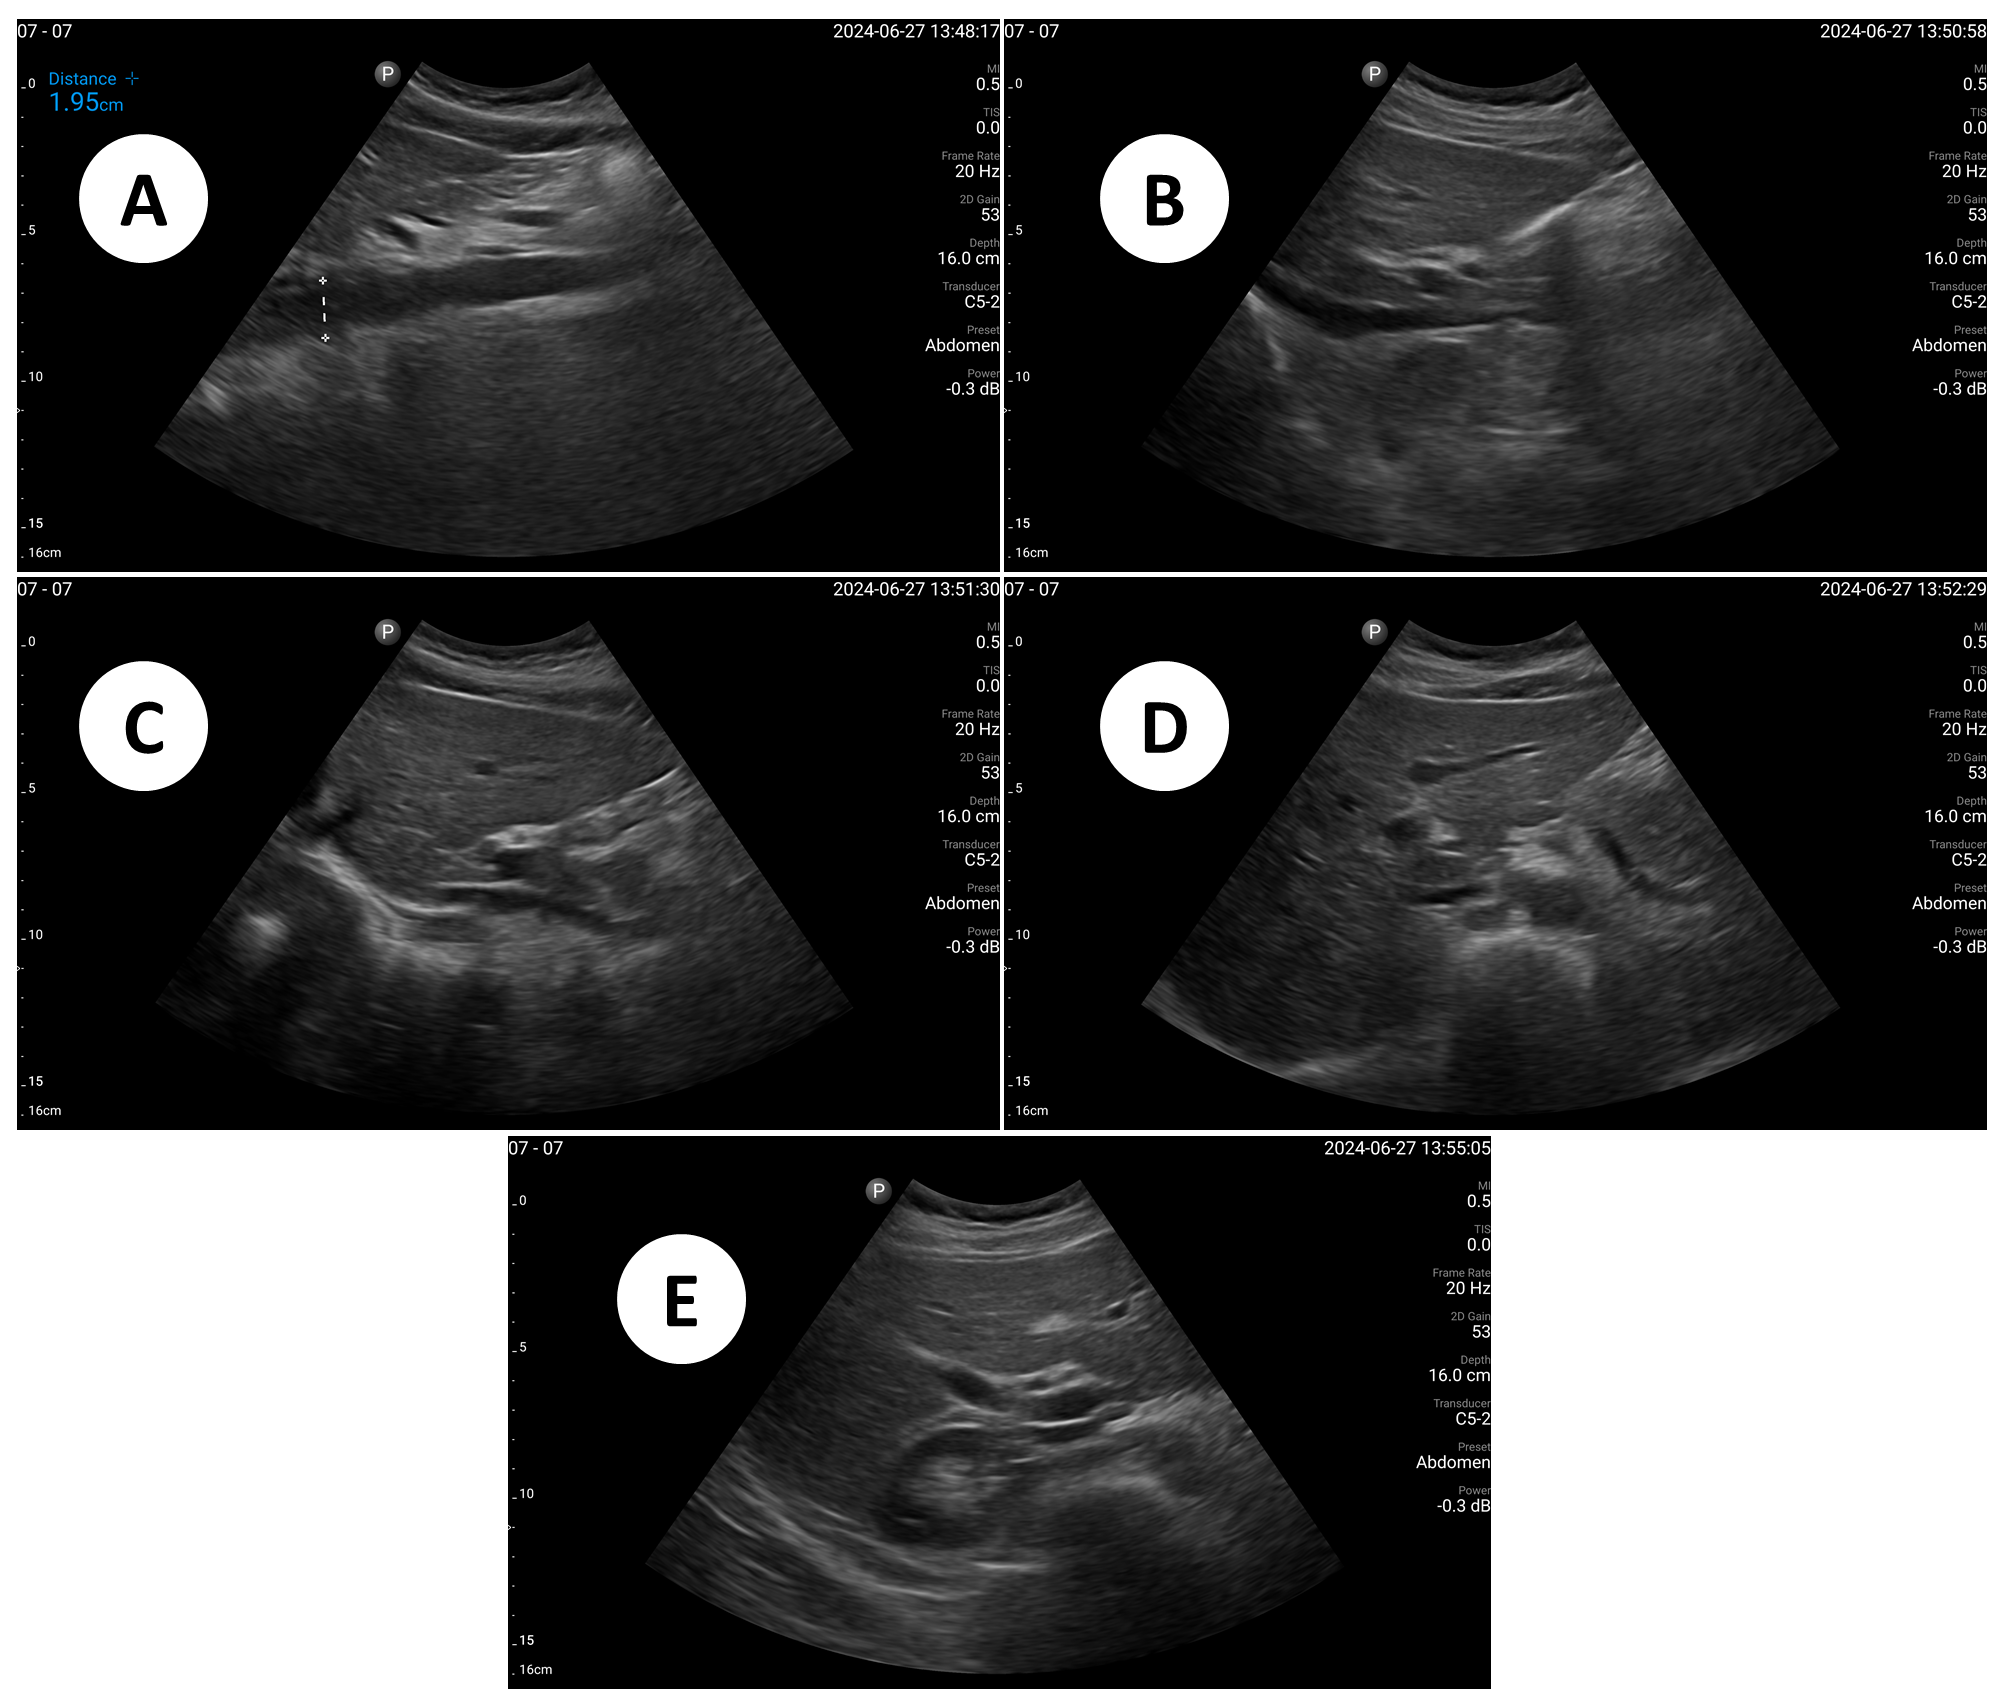

Refer to caption

Figure 6: Example US images acquired in the study using the human teleoperation system. A: Proximal aorta (AP diameter). B: IVC - longitudinal. C: Left lobe of liver - long axis. D: Left lobe of liver - transverse. E: Right portal vein - transverse.

The sonographers completed 11 abdominal US scans, each with 5 target images and measurements for a total of 55 images. An example image of each of the targets acquired during these tests is shown in Fig. 6. The image quality results are shown in Fig. 7 which illustrates the total number of each score given by both radiologists. The results excluding the first 2 scans are also shown in Fig. 8 because some technical issues such as internet disconnections occurred during these scans which may have affected the results. Of the 55 target images, 7 were considered missing by at least one of the radiologists. Of these missing targets, 3 were not captured due to large amounts of bowel gas and body habitus while one was seen but the sonographer did not capture and save the image. When considering only the images that were captured, a mean score of 4.28±0.95plus-or-minus4.280.954.28\pm 0.954.28 ± 0.95 out of 5 was obtained and 91.7% of the images were scored 3absent3\geq 3≥ 3 by both radiologists. 31.3% of the images were scored 5 by both radiologists, indicating the image quality was good and meaningful image interpretation was easy.